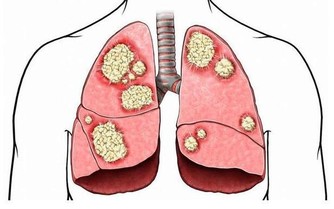

在兒童腫瘤數據中,超過一半的數據由白血病“貢獻”,而且還在以每年3-4萬的速度往上增加。在治療的同時我們也在深思,為什麼受傷的總是孩子?

孩子身體有效,但是細胞很活躍,代謝和更新的速度比成年人快,如果外界環境中存在不良因素,細胞在分裂的過程中就可能“出差錯”,最後形成癌細胞。